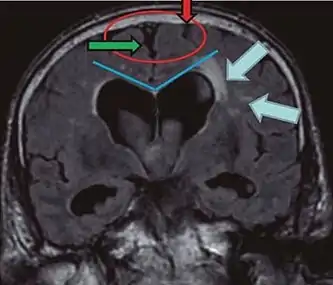

- Imaging from magnetic resonance imaging (MRI) or computed tomography (CT) is needed to demonstrate enlarged ventricles and no macroscopic obstruction to cerebrospinal fluid flow. Imaging should show an enlargement to at least one of the temporal horns of lateral ventricles, and impingement against the falx cerebri resulting in a callosal angle ≤ 90° on the coronal view, showing evidence of altered brain water content, or normal active flow (which is referred to as "flow void") at the cerebral aqueduct and fourth ventricle.

| Normal pressure hydrocephalus | Brain atrophy | |

| Preferable projection | Coronal plane at the level of the posterior commissure of the brain. | |

| Modality in this example | CT | MRI |

| CSF spaces over the convexity near the vertex (red ellipse | Narrowed convexity ("tight convexity") as well as medial cisterns | Widened vertex (red arrow) and medial cisterns (green arrow) |

| Callosal angle (blue V) | Acute angle | Obtuse angle |

| Most likely cause of leucoaraiosis (periventricular signal alterations, blue arrows |

Transependymal cerebrospinal fluid diapedesis | Vascular encephalopathy, in this case suggested by unilateral occurrence |

MRI scans are the preferred imaging. The distinction between normal and enlarged ventricular size by cerebral atrophy is difficult to ascertain. Up to 80% of cases are unrecognized and untreated due to difficulty of diagnosis.[9] Imaging should also reveal the absence of any cerebral mass lesions or any signs of obstructions. Although all patients with NPH have enlarged ventricles, not all elderly patients with enlarged ventricles have primary NPH. Cerebral atrophy can cause enlarged ventricles, as well, and is referred to as hydrocephalus ex vacuo.